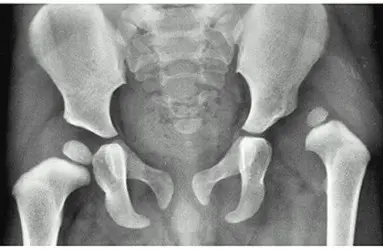

- Gelişimsel Kalça Displazisi (GKD)